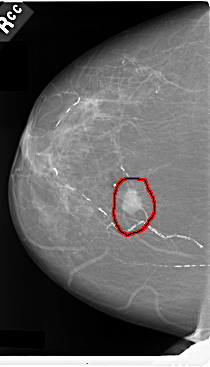

FILE: C_0031_1.RIGHT_CC.OVERLAY

TOTAL_ABNORMALITIES 1

ABNORMALITY 1

LESION_TYPE MASS SHAPE IRREGULAR MARGINS SPICULATED

ASSESSMENT 5

SUBTLETY 5

PATHOLOGY MALIGNANT

TOTAL_OUTLINES 1

BOUNDARY